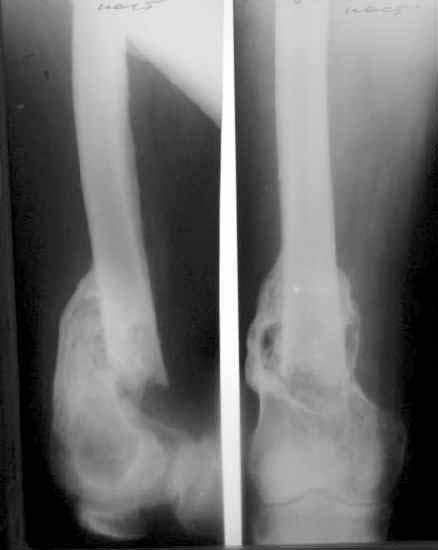

A male 53 years old Nov. 25, 2002 sustained multiple injuries including pelvic ring lesion, # of the left acetabulum, # of the right femoral shaft, left patella, also left ankle and right forearm. He was initially treated elsewhere on traction, the ankle in plastre cast and the forearm with ex-fix.

Referenced to us Mar. 25, 2003 - 4 months after the injury with healed femur, ankle and forearm. Pelvic external fixator was applied to correct the ring shape. Apr 28, 2003 the symphisys was plated and acetabular ORIF was performed mostly to prepare it for later THA.

Now he walks with crutches, with pain in affected hip, radiologic changes of the head are in progress. In other words the joint is ready for replacement.

X-rays attached.